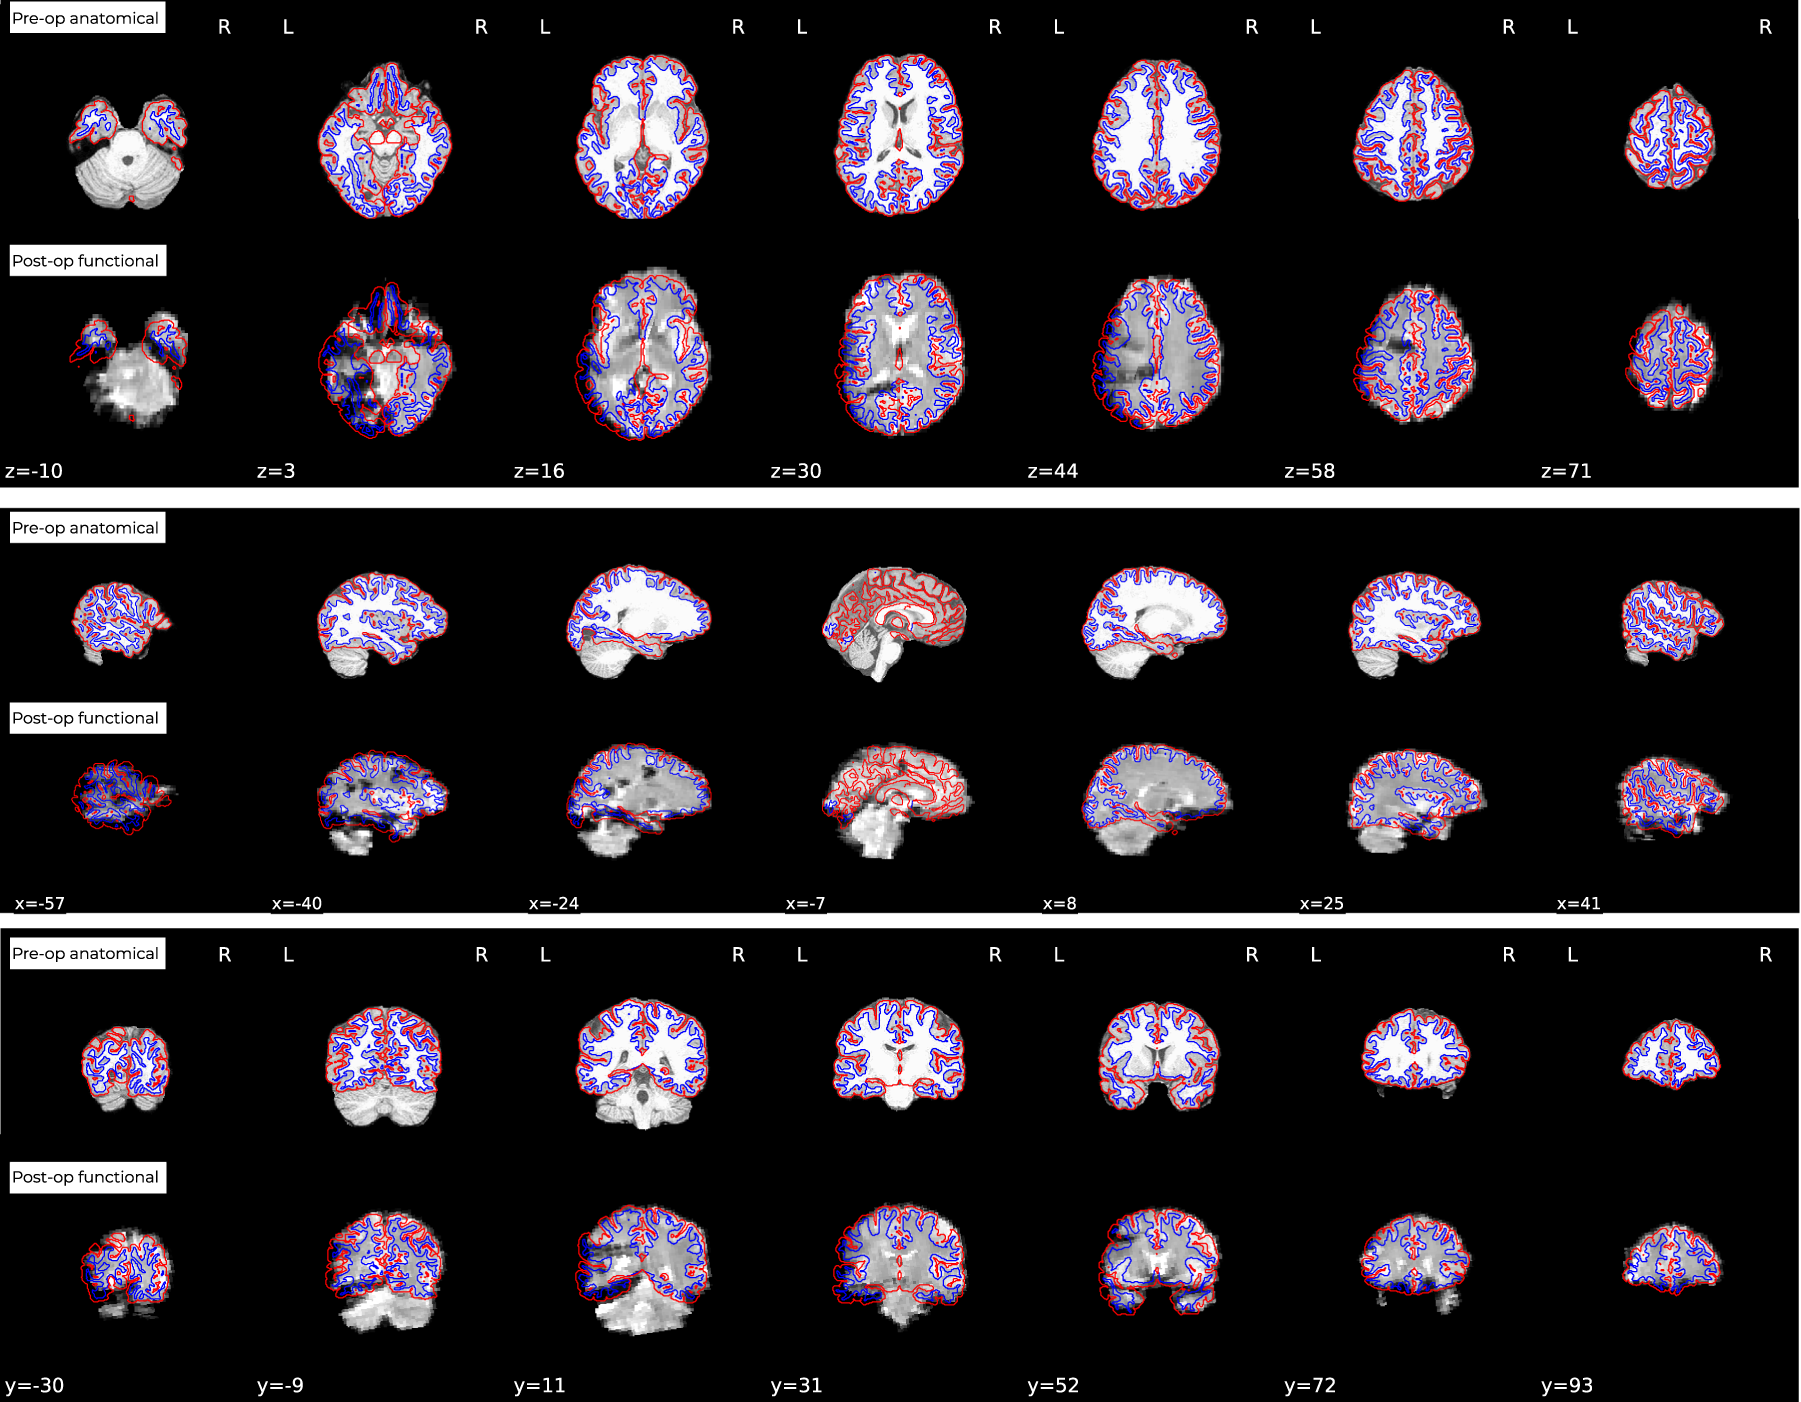

Fig. 4

Example of fMRIPrep report of co-registration of post-op functional and pre-op structural images shows extent of noise and distortion on es-fMRI images. Here we can observe that large portions of the left hemisphere of the functional data contains substantial artifacts. However fMRIPrep still co-registers the images adequately despite the distortion. Users of this dataset are strongly encouraged to carefully check each individual subject’s data and co-registration before proceeding to use it in analyses.